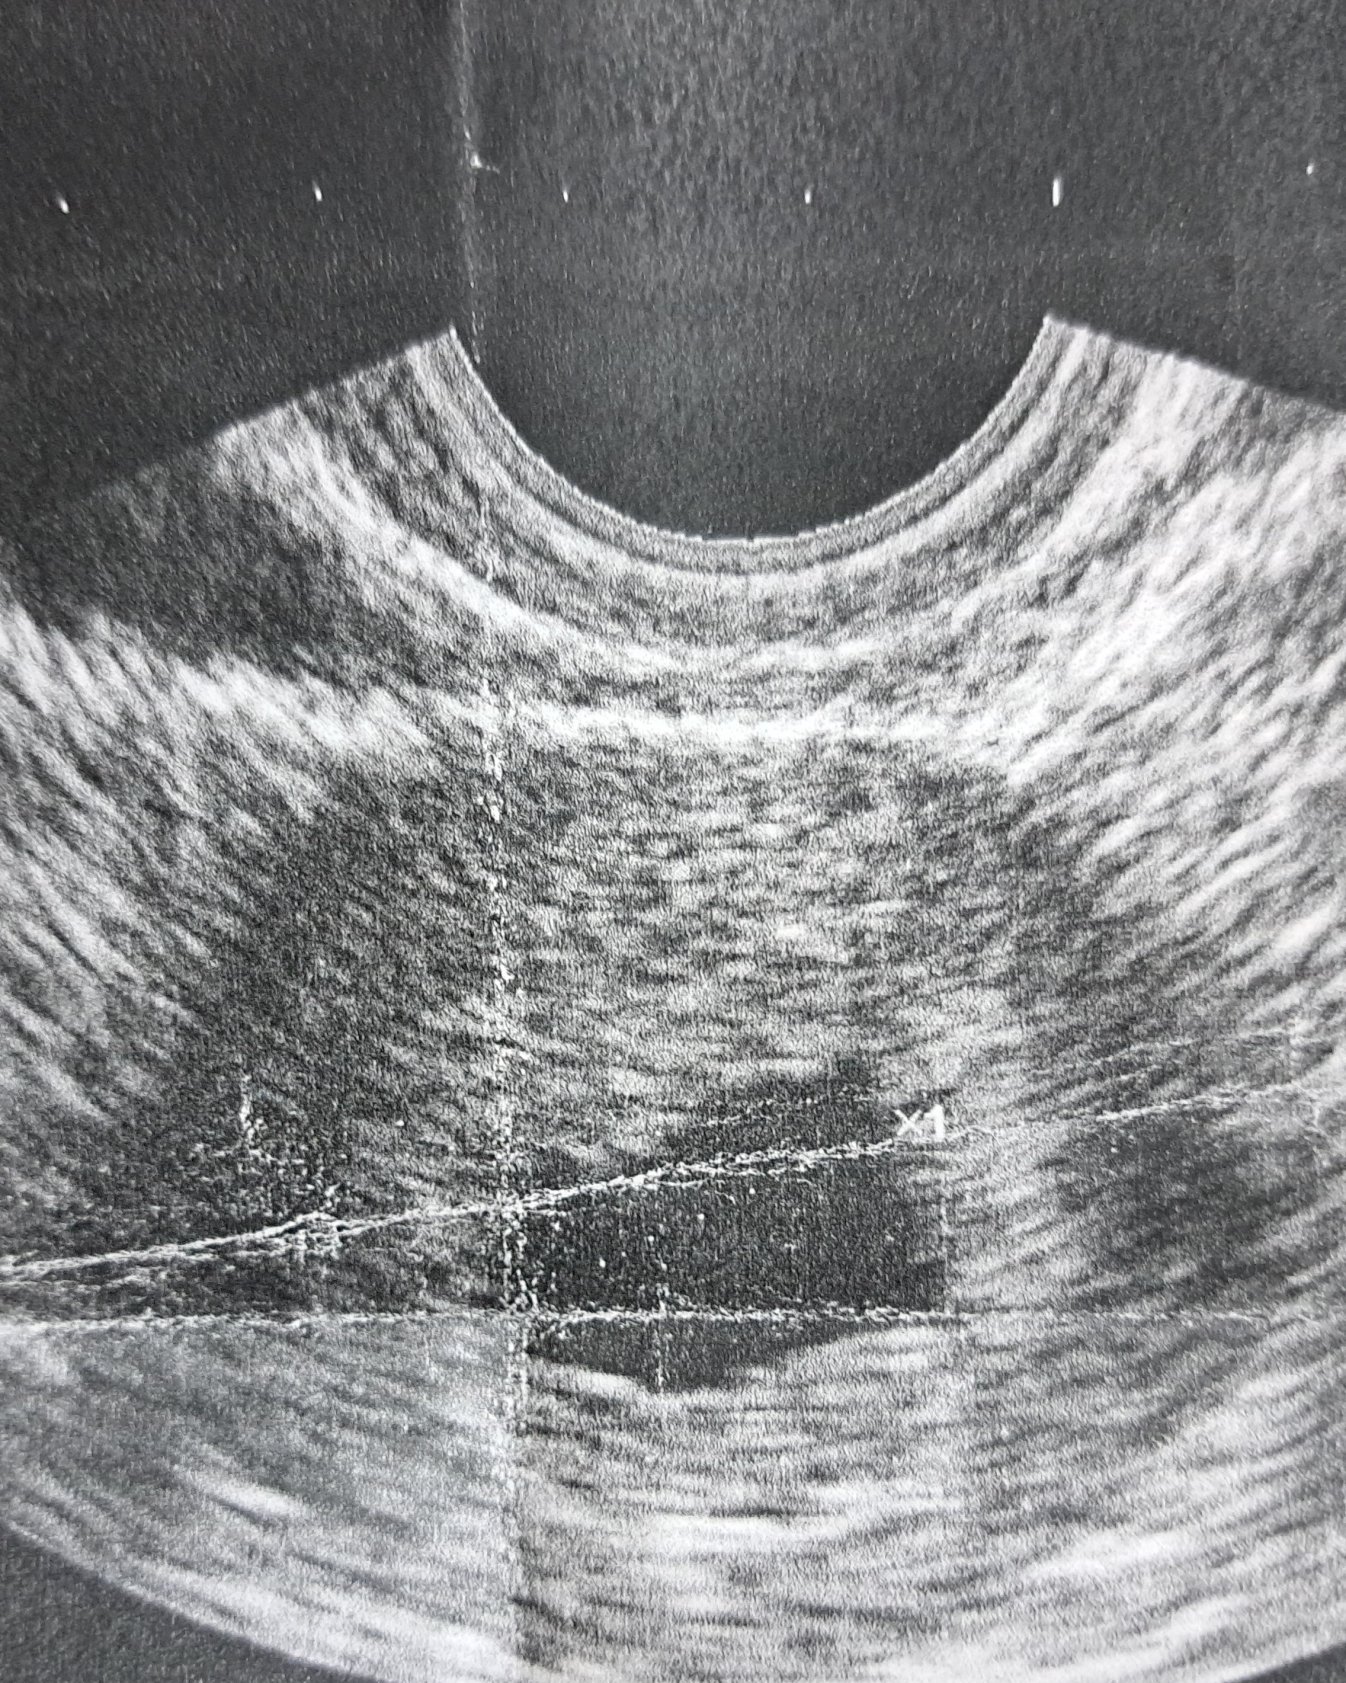

Здравейте! Днес бях на преглед и докторът каза, че вижда "отчасти" сърдечни пулсации, но това което аз видях на екрана не беше в плодния сак, а над него. В 7 г.с. съм. Пише, че плодния сак е 18.7мм. Последна менструация на 25.10. Според вас всичко наред ли изглежда? Може би аз просто не разбирам.

В 7 г.с. би трябвало да се вижда ембрион и да се чуе пулс. Съжалявам, но на тази снимка не се вижда ембрион. То и ехографа е много зле, но мисля, че сака е празен. Няма как "отчасти" или има, или няма пулс, или е много слаб, което не говори добре.

А не се ли видяха пулсациите е червено и синьо? При мен и с двете бременности така първо се изобразиха, а не пулсираща точка. Аз иначе нищо не виждам на тази снимка освен сакче, но и качеството в доста зле.

Според мен в 7 г.с. трябва поне ембрион да се вижда, но може и да се крие. Аз тук не виждам, но не съм и лекар. Иди наистина на място с по-добър ехограф.

С коремен ли те гледа ? Изключително лошо качество на снимката . Апаратурата изглежда доста стара .

Марипоса , там където пише едно , би трябвало да е маркирал плода . Едва ли щом е лекар със стаж и име , не може да разбере кога има проблем . Вероятно просто техниката е кофти . За да си по-спокойна , може да отидеш на второ мнение , но наистина при док с добър ехограф .